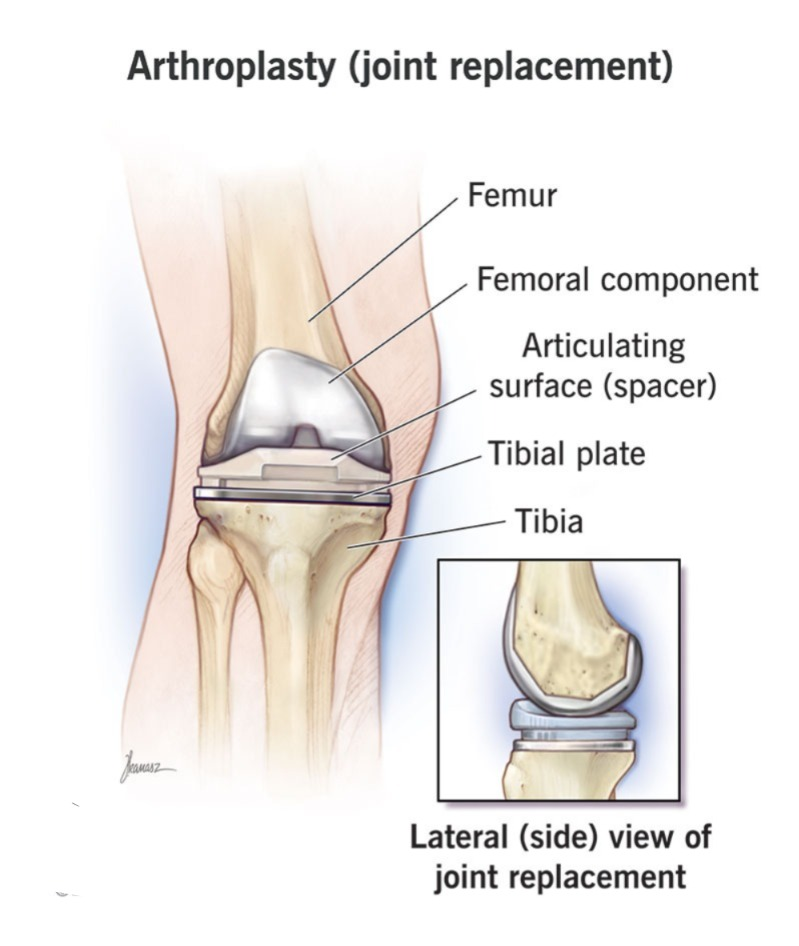

16) define arthroplasty (આથૅરોપ્લાસ્ટિ ને વ્યાખ્યાયિત કરો):=

• આ એક જોઈન્ટ રિપ્લેસમેન્ટ છે કે જેમાં આર્ટિફિશિયલ જોઈન્ટ એટલે કે પ્રોસ્થેસિસ નો ઉપયોગ કરવામાં આવે છે.